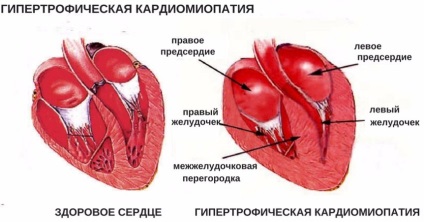

Cardiomiopatia hipertrofica este o forma comuna de boli de inima este însoțită de îngroșare, strat hipertrofică musculare schimbare de organe. Boala este caracterizată prin deteriorarea nutriție miocardic, a redus volumul de sânge. Boala poate purta un caracter primar, și, de asemenea, se dezvolta ca urmare a unor boli asociate.

Ce se întâmplă cu inima unei pisici în patologia

Perturbarea pentru funcționarea mușchiului inimii începe după organul apar modificări morfologice specifice. Odată cu dezvoltarea distrugerii patologice cardiomiopatie hipertrofică expuse ventriculul stâng în primul rând și septul interventricular.

Gena defect conduce la faptul că organismul nu este în măsură să producă cantități suficiente de o proteina specifica - miozină, care constituie baza miocardului. Organismul incepe sa compenseze lipsa de fibre musculare țesutului conjunctiv. Peretele miocardului se îngroașă. Corp ca cicatrici.

Îngroșarea peretelui miocardic care duce la faptul că a redus volumul ventriculului stâng, iar atriul de multe ori la stânga. În plus, țesutul conjunctiv reduce elasticitatea și extensibilitatea a inimii. Există o slăbire a funcției de organe de pompare.

Îngroșarea miocardului determină sângele stagnează în atrii și supapa atrioventricular perturbat. Obstrucția aortei apare, există un deficit circulator.

Dezvoltarea cardiomiopatie hipertrofică afectează toate părțile inimii și circulația sângelui afectează corpul ca un întreg. Acest lucru se datorează faptului că există un spasm al fluxul sanguin periferic, deversează vasele sanguine pulmonare. Pacient cheaguri de sânge de animale au format ca urmare a fluxului sanguin lent în camerele întinse ale inimii.